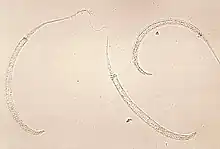

Photomicrograph of larvae | |

D. medinensis L1 larvae are found in fresh water, where they are ingested by copepods (small crustaceans) of the genus Cyclops. Within the copepod, the D. medinensis larvae develop to an infective L3 stage within 14 days.[9] When the infected copepod is ingested by a mammalian host drinking unfiltered water, the copepod is then dissolved by stomach acid and dies and the D. medinensis larvae are released and migrate through the wall of the mammalian intestine, and enter the abdominal cavity and retro-peritoneal space, where they mature into adults. After maturing and mating within the host, the males die and females (length 70–120 cm) migrate in subcutaneous tissue towards the skin's surface. Around a year after the infection, the female causes the formation of a blister on the skin's surface, generally on the lower extremities, though occasionally on the hand or scrotum. When the blister ruptures, the female slowly emerges over the course of several days or weeks.[9] This causes extreme pain and irritation to the host. During those few days to hours before the worm exits the skin, the person may develop a fever, pain, or swelling in that area. When the host — in an attempt to alleviate the excruciating burning pain — submerges the affected body part in water, the female releases thousands of larvae into the water. From here, the larvae infect copepods, continuing the life cycle.[9] After the worm exits the skin the wound caused by the emerging worm often develops a secondary bacterial infection. Permanent damage can occur if the infection goes untreated around a joint. Most cases occur in areas without access to health care facilities.[10]